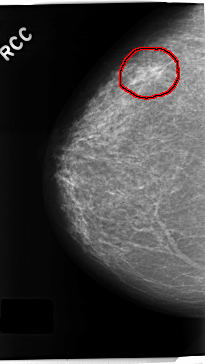

C_0230_1.RIGHT_CC

FILE: C_0230_1.RIGHT_CC.OVERLAY

TOTAL_ABNORMALITIES 1

ABNORMALITY 1

LESION_TYPE MASS SHAPE IRREGULAR MARGINS SPICULATED

ASSESSMENT 5

SUBTLETY 5

PATHOLOGY MALIGNANT

TOTAL_OUTLINES 1

BOUNDARY